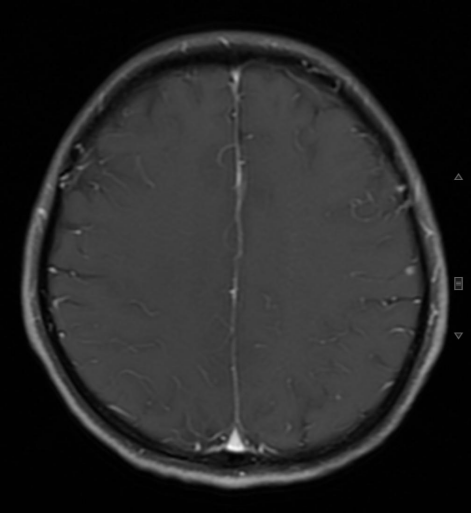

• 颅脑 MRI:左侧顶叶结节灶,直径约 0.5 cm 强化结节灶,转移可能性大。临床表现:无恶心、呕吐、头痛、视物模糊、血压升高、意识障碍等脑转移相关临床表现。

图片

图 4 颅脑 MRI